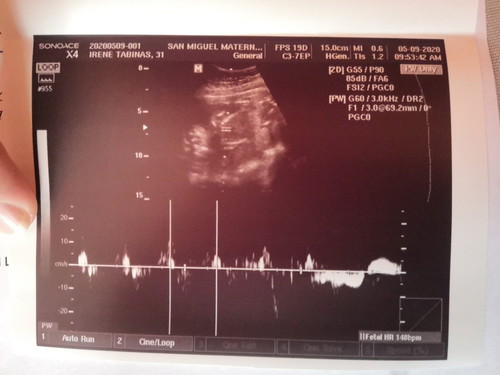

Placental Previa Grade 1 and Breech position.

Mga kumare, ako 'to si kumpare. Itatanong ko lang, second ultrasound ni misis nung May 9 (Saturday), Placenta previa grade 1 and breech position ni baby. 17 weeks pregnant si misis. Normal po kaya yun? Sabi ng doctor mababa daw yung placenta pero magbabago pa daw yun at yung sa position naman ni baby eh iikot pa, masyado pang maaga.